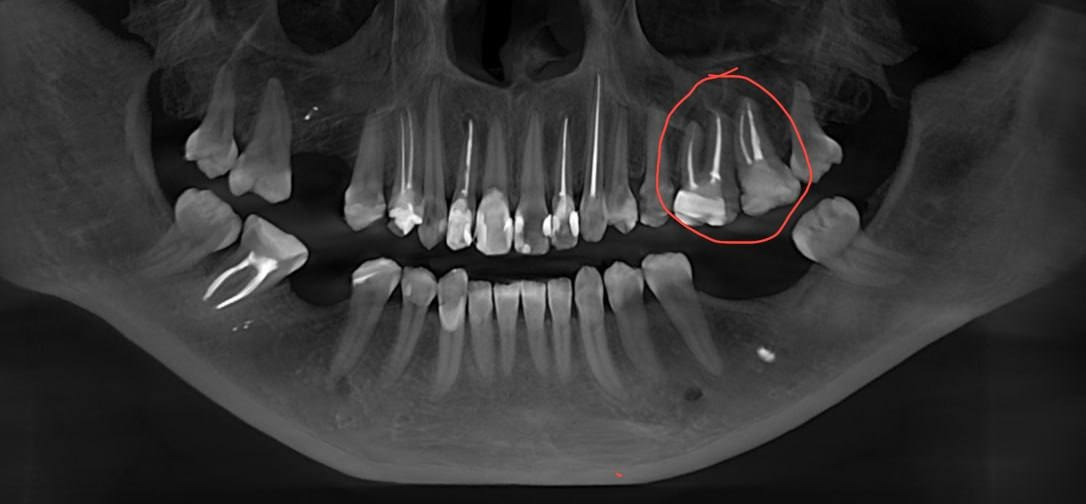

Пролечить каналы и кисты

Здравствуйте, кисты над корнямиз убов, возможно заложить лекарство и переделать каналы или как один зубной посоветовала дождаться пока выпадут и имплантация?

29 лет, девушка, в целом, наследство достались не очень зубы, кисты часто, имплантация пугает, но в перспективе выглядит будто бы самым адекватным вариантом